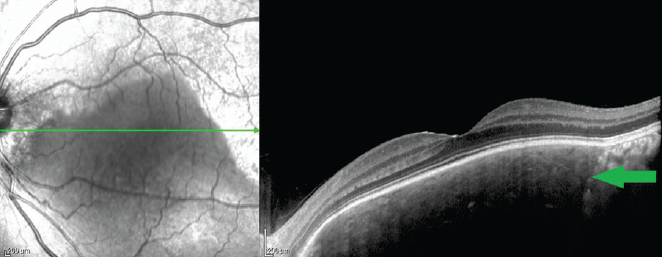

In our cases, the acquired tomographic signs were characteristic of SCC, namely the chorioretinal complex elevation with an uneven tuberous surface, the presence of a “peak-shaped” contour of the Bruch’s membrane, a choroid thinning with increased signal hyperreflectivity, the presence of damage zones in the Bruch’s membrane, disorders of the retinal architectonics (thinning due to atrophy of the retinal outer layers in the zones of the Bruch’s membrane “peak-shaped” contour and an increase in the retinal thickness because of expansion of the nuclear layers in the Bruch’s membrane retraction zones) (Figs. 3, 4). Under the thinned choroid, zones of a local moderately hyporeflective structure were visible (Fig. 5), which is considered as a distinct sign of scleral inner layers lesions [3]. Furthermore, the visualization of the outer border of the choroid was disturbed in the areas of the retinal lesion.

Fig. 3. Optical coherence tomography of the patient B. (72 years old). Horizontal scan across sclerochoroidal calcification. Green arrows – “spiky” Bruch’s membrane profile, blue arrows – Bruch’s membrane “entrapment” area

Рис. 3. Оптическая когерентная томография пациентки Б., 72 года. Горизонтальный срез через зону склерохориоидальной кальцификации. Зелёные стрелки — «пикообразный» профиль мембраны Бруха; синяя стрелка — зона «западения» мембраны Бруха

Fig. 5. Optical coherence tomography of the patient Sh. (59 years old). Horizontal scan across sclerochoroidal calcification. Arrow – thinning of the choroid and the zone of Bruch’s membrane “entrapment”; dotted line – hyporeflective structure under a thinned choroid

Рис. 5. Оптическая когерентная томография пациентки Ш., 59 лет, горизонтальный срез через зону склерохориоидальной кальцификации. Стрелка — резкое истончение хориоидеи и зона «западения» мембраны Бруха; пунктир — гипорефлективная структура под истончённой хориоидеей